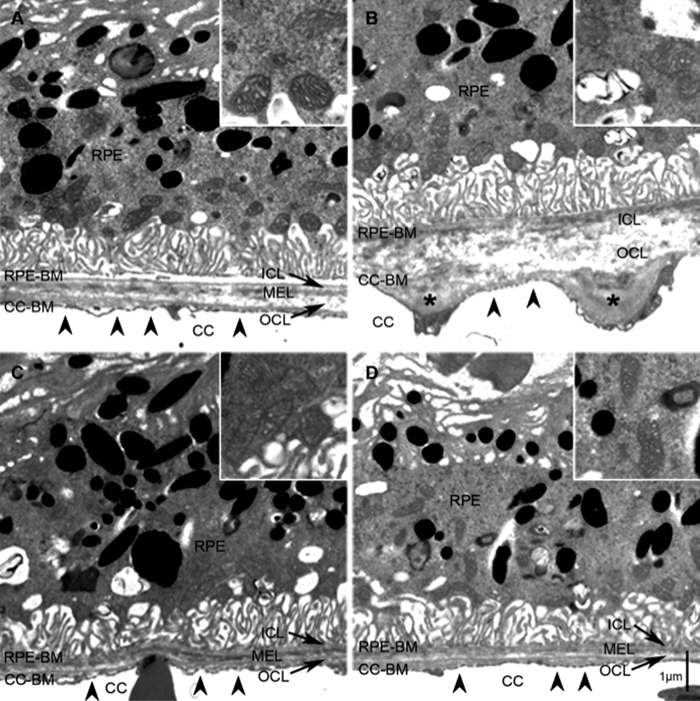

Alex Woodell, Beth Coughlin, Kannan Kunchithapautham, Sarah Casey, Tucker Williamson, W. Drew Ferrell, Carl Atkinson, Bryan Jones and Baerbel Rohrer have a new manuscript out, The Alternative Complement Pathway Deficiency Amerliorates Chronic Smoked-Induced Functional And Morphological Ocular Injury in PLOS One.

The short story is: Don’t smoke. But then you knew that. Where this paper contributes is that it provides clear findings that show ocular pathologies generated by cigarette smoke are dependent upon activation of the immune system, in particular complement and the alternative pathway which are critical findings in the treatment of AMD.